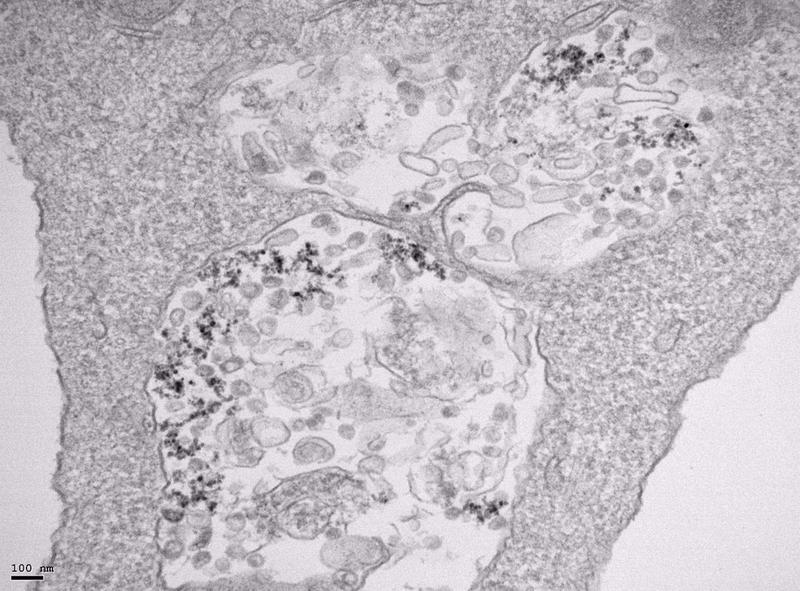

Imagen de microscopía de transmisión electrónica de células infectadas con SARS-CoV-2 y tratadas con nanopartículas de óxido de hierro. - CNB-CSIC

Domingo F. Barber, investigador del CNB-CSIC, detalla que ya se había visto que las nanopartículas de óxido se acumulan en el interior de las células en vesículas llamadas lisosomas.

"Es ahí donde con el tiempo se degradan, induciendo estrés oxidativo y alterando el metabolismo intracelular del hierro. Dado que el estrés oxidativo afecta a la estabilidad de la membrana lipídica del virus de la gripe y reduce su capacidad de infección, pensamos que podría ocurrir lo mismo con el SARS-CoV-2 y decidimos tratar células infectadas con SARS-CoV-2 con diferentes tipos de nanopartículas, unas producidas por el grupo del ICMM-CSIC y otras comerciales, como son un antianémico y un agente de contraste de resonancia magnética", indica Barber.